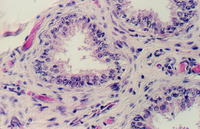

- Prostate